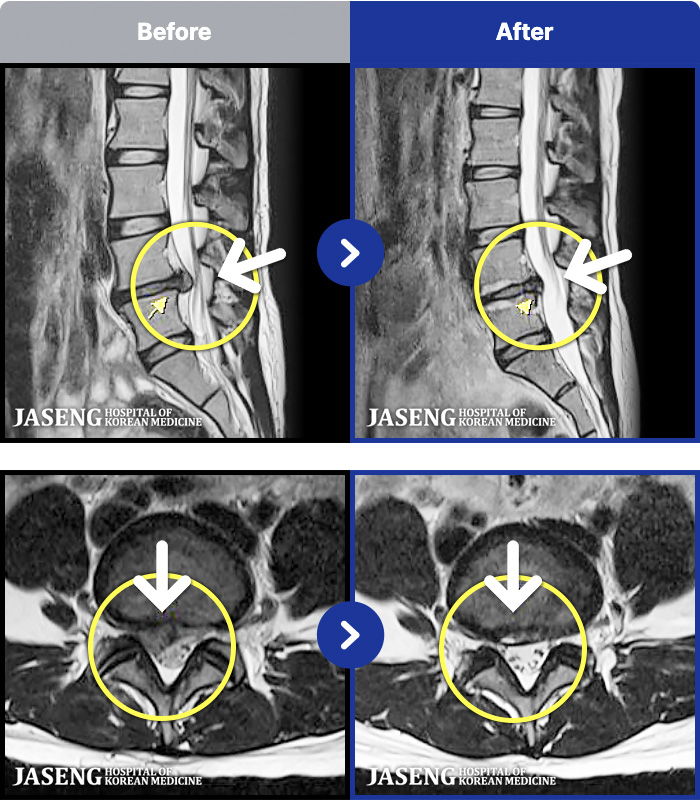

- MRI ġ

MRI ġ

94 MRI ũ ʸ Ȯϼ.

㸮 ϻ .